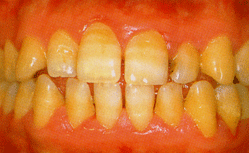

| 2 |

プラークが歯石になり、歯石は大きくなって、歯根膜が溶け歯肉溝のなかにも広がってゆく。歯肉溝はだんだん深くなり、歯肉の弾力性がなくなって、歯周ポケットと呼ばれる空間ができる。炎症も進み、歯槽骨の破壊も始まってくる。 |

| 歯周炎 |

| 約3ヶ月後、ブラッシング指導などにより歯周炎が改善された例 |